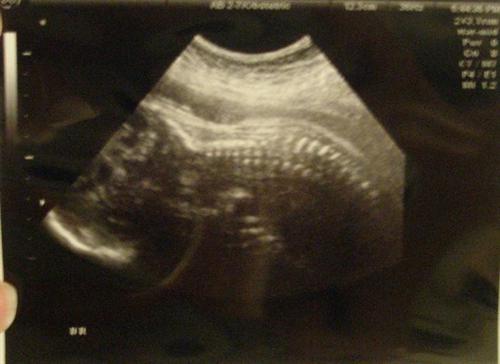

Here are some pics. We couldnt get a face shot because of her position:

Foot and some other stuff:

She is measuring exactly at 29 weeks to the day which is where I am at the very moment. Her femur is measuring at 29 weeks and 3 days and she weighs 3 pounds leading me to believe that her mother's amazon genes are kicking in overdrive. DH's mom and sisters are also tall women too so basketball scholarships could work!

My BP and HER heartbeat is excellent. We saw the chambers of her heart.

It seems as if Ed-lie is breech at the moment but it doesnt mean much though it does explain why I feel she has been tap dancing in my vag. There is no reason to think she won't turn around as I have a ways to go yet.

Thanks ladies. The doctor was really impressed with Ed's ability to see a foot. I was too!